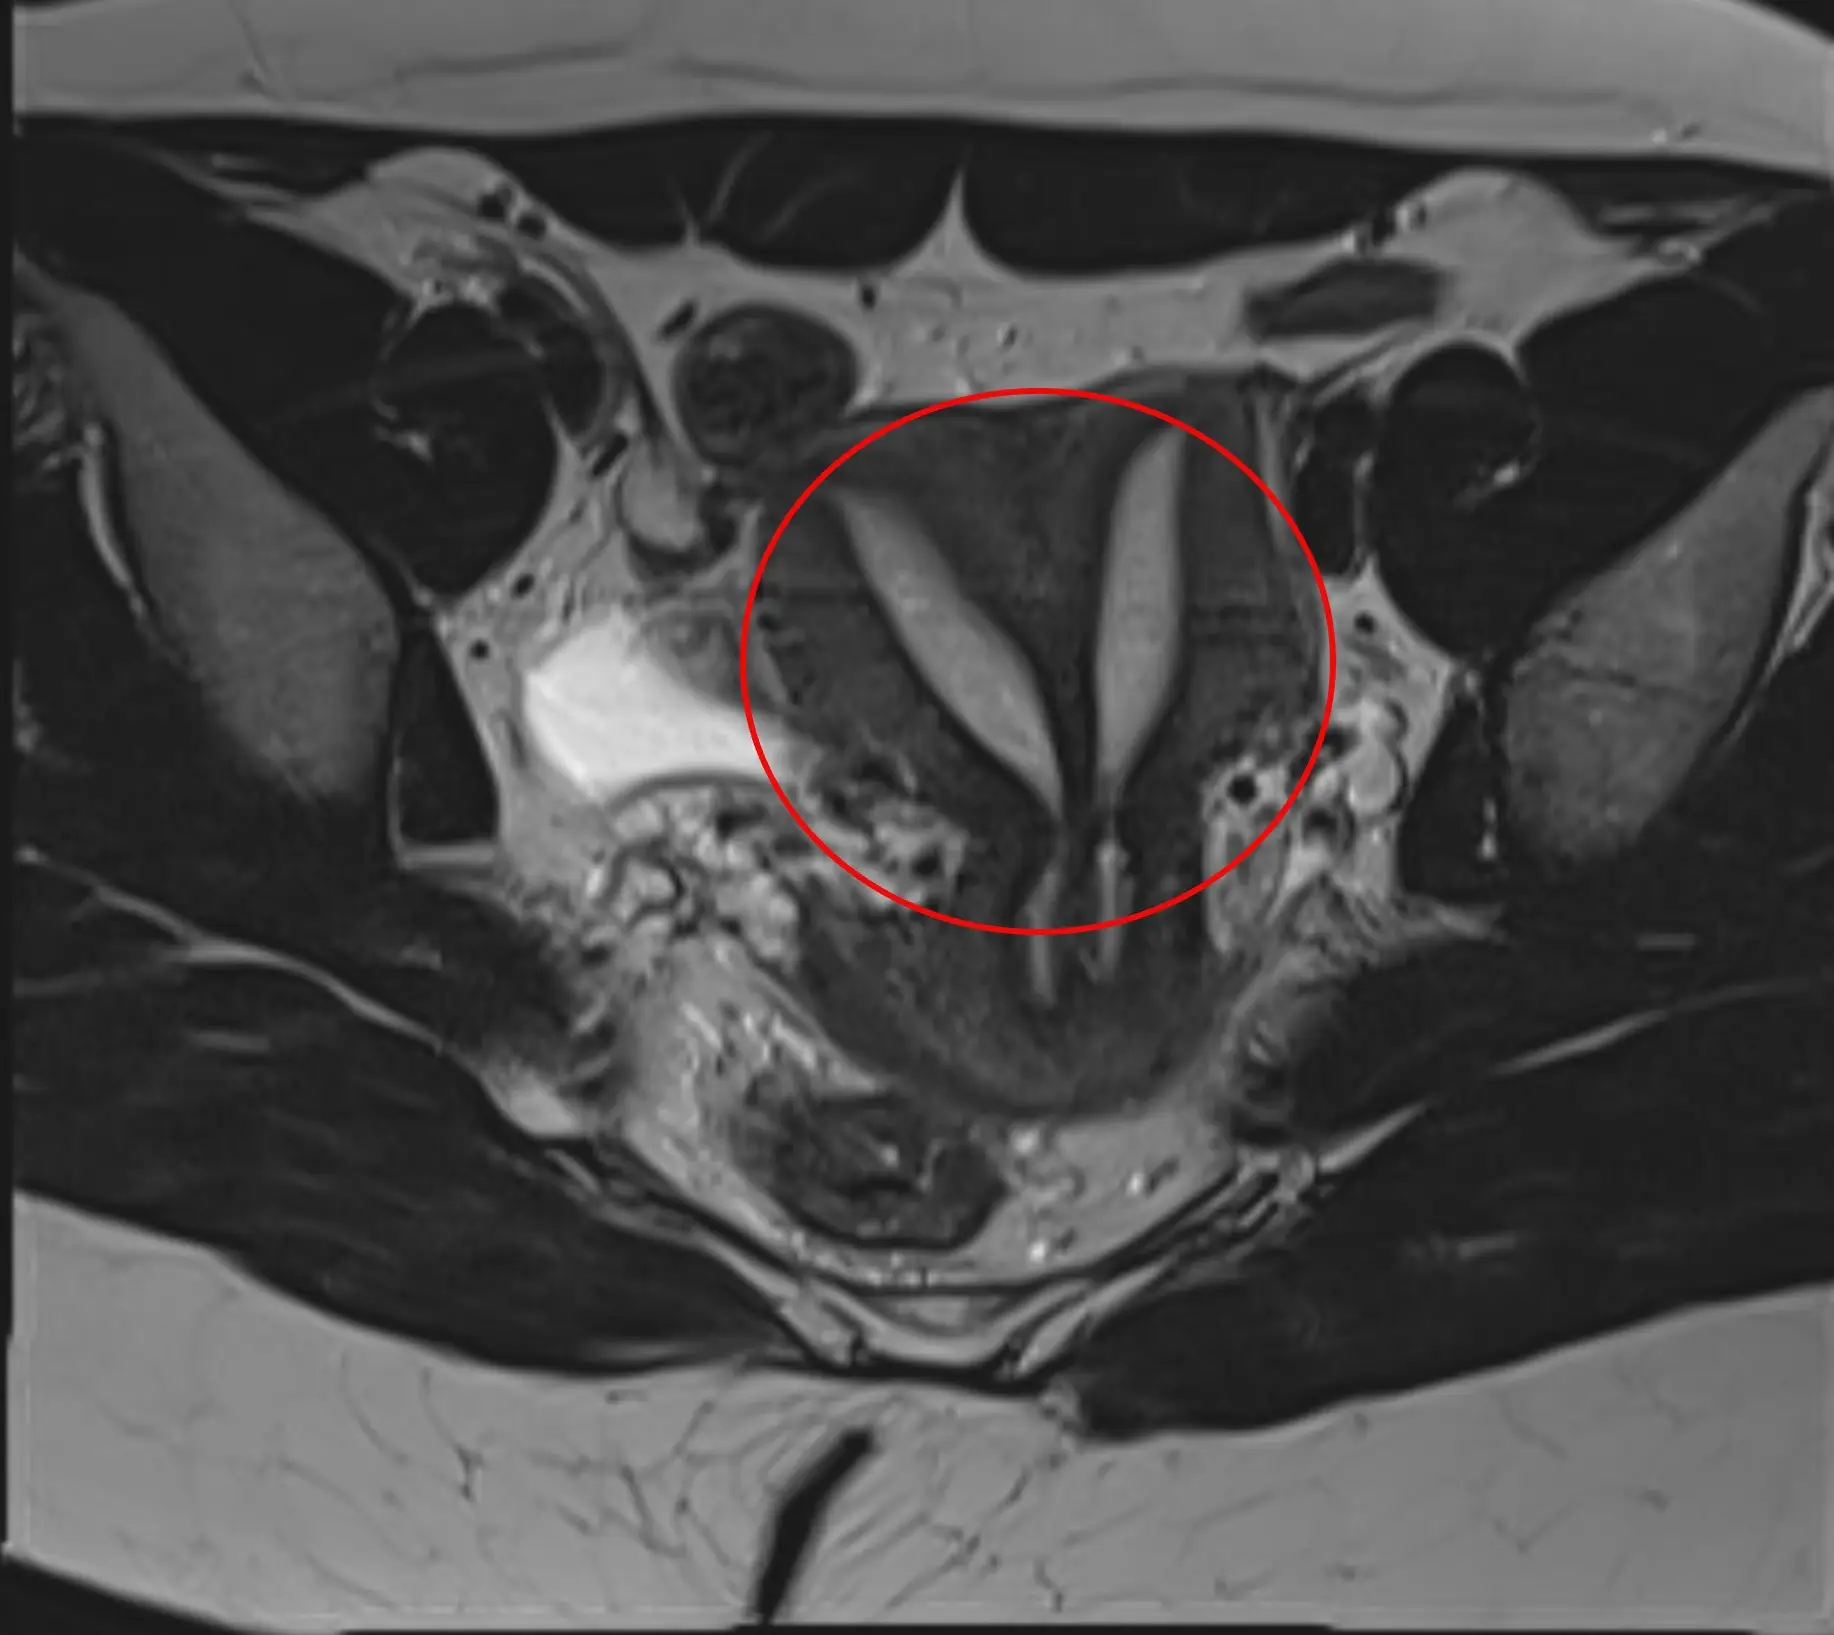

A 27-year-old woman has shared what it's like to have complete uterus didelphys. Per Cleveland Clinic, this is a rare congenital condition where you’re born with two uteruses.

It's also referred to as 'double uteruses' and only affects around 0.3 percent of Americans.

She penned on the social media platform's famous 'Ask Me Anything' (AMA) page: "I (27F) have complete uterus didelphys, resulting in 2 uteruses, 2 cervixes, and almost 2 vaginas. (We joke that I have 1 & a half of them.) I had suspicions something was off for a long time, but didn’t get diagnosed until I was in my early-mid twenties. I have given birth to one child. Ask me anything!"